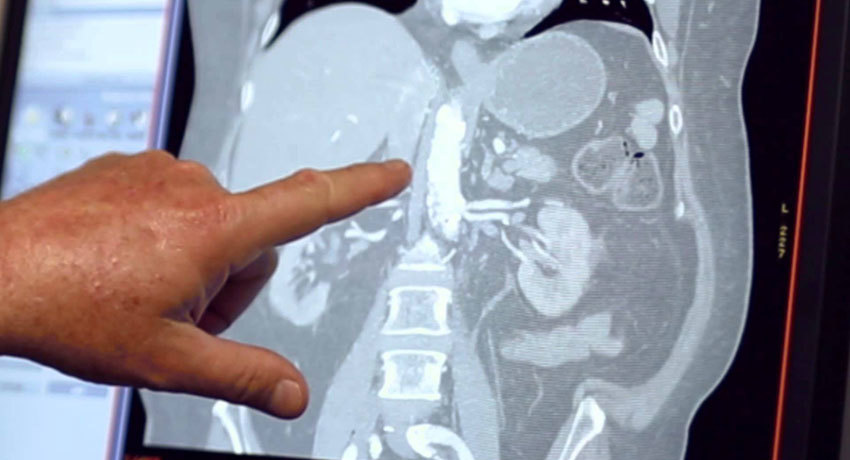

Чтобы обнаружить опухоли в печени, применяют различные методы визуализации. Ультразвуковое исследование не очень информативно, во время него не всегда удается точно определить очаги.

Довольно информативна ангиография — рентгенография печени с введением контрастного вещества в кровеносные сосуды. Она обладает чувствительностью 65% и может обнаруживать очаги диаметром менее 5 мм. Однако, минус этого метода диагностики в том, что он является инвазивным, поэтому в настоящее время его применяют не так часто.

Чувствительность компьютерной томографии составляет 70–85%. Во время нее также используют контрастирование. Практически так же эффективна магнитно-резонансная томография.